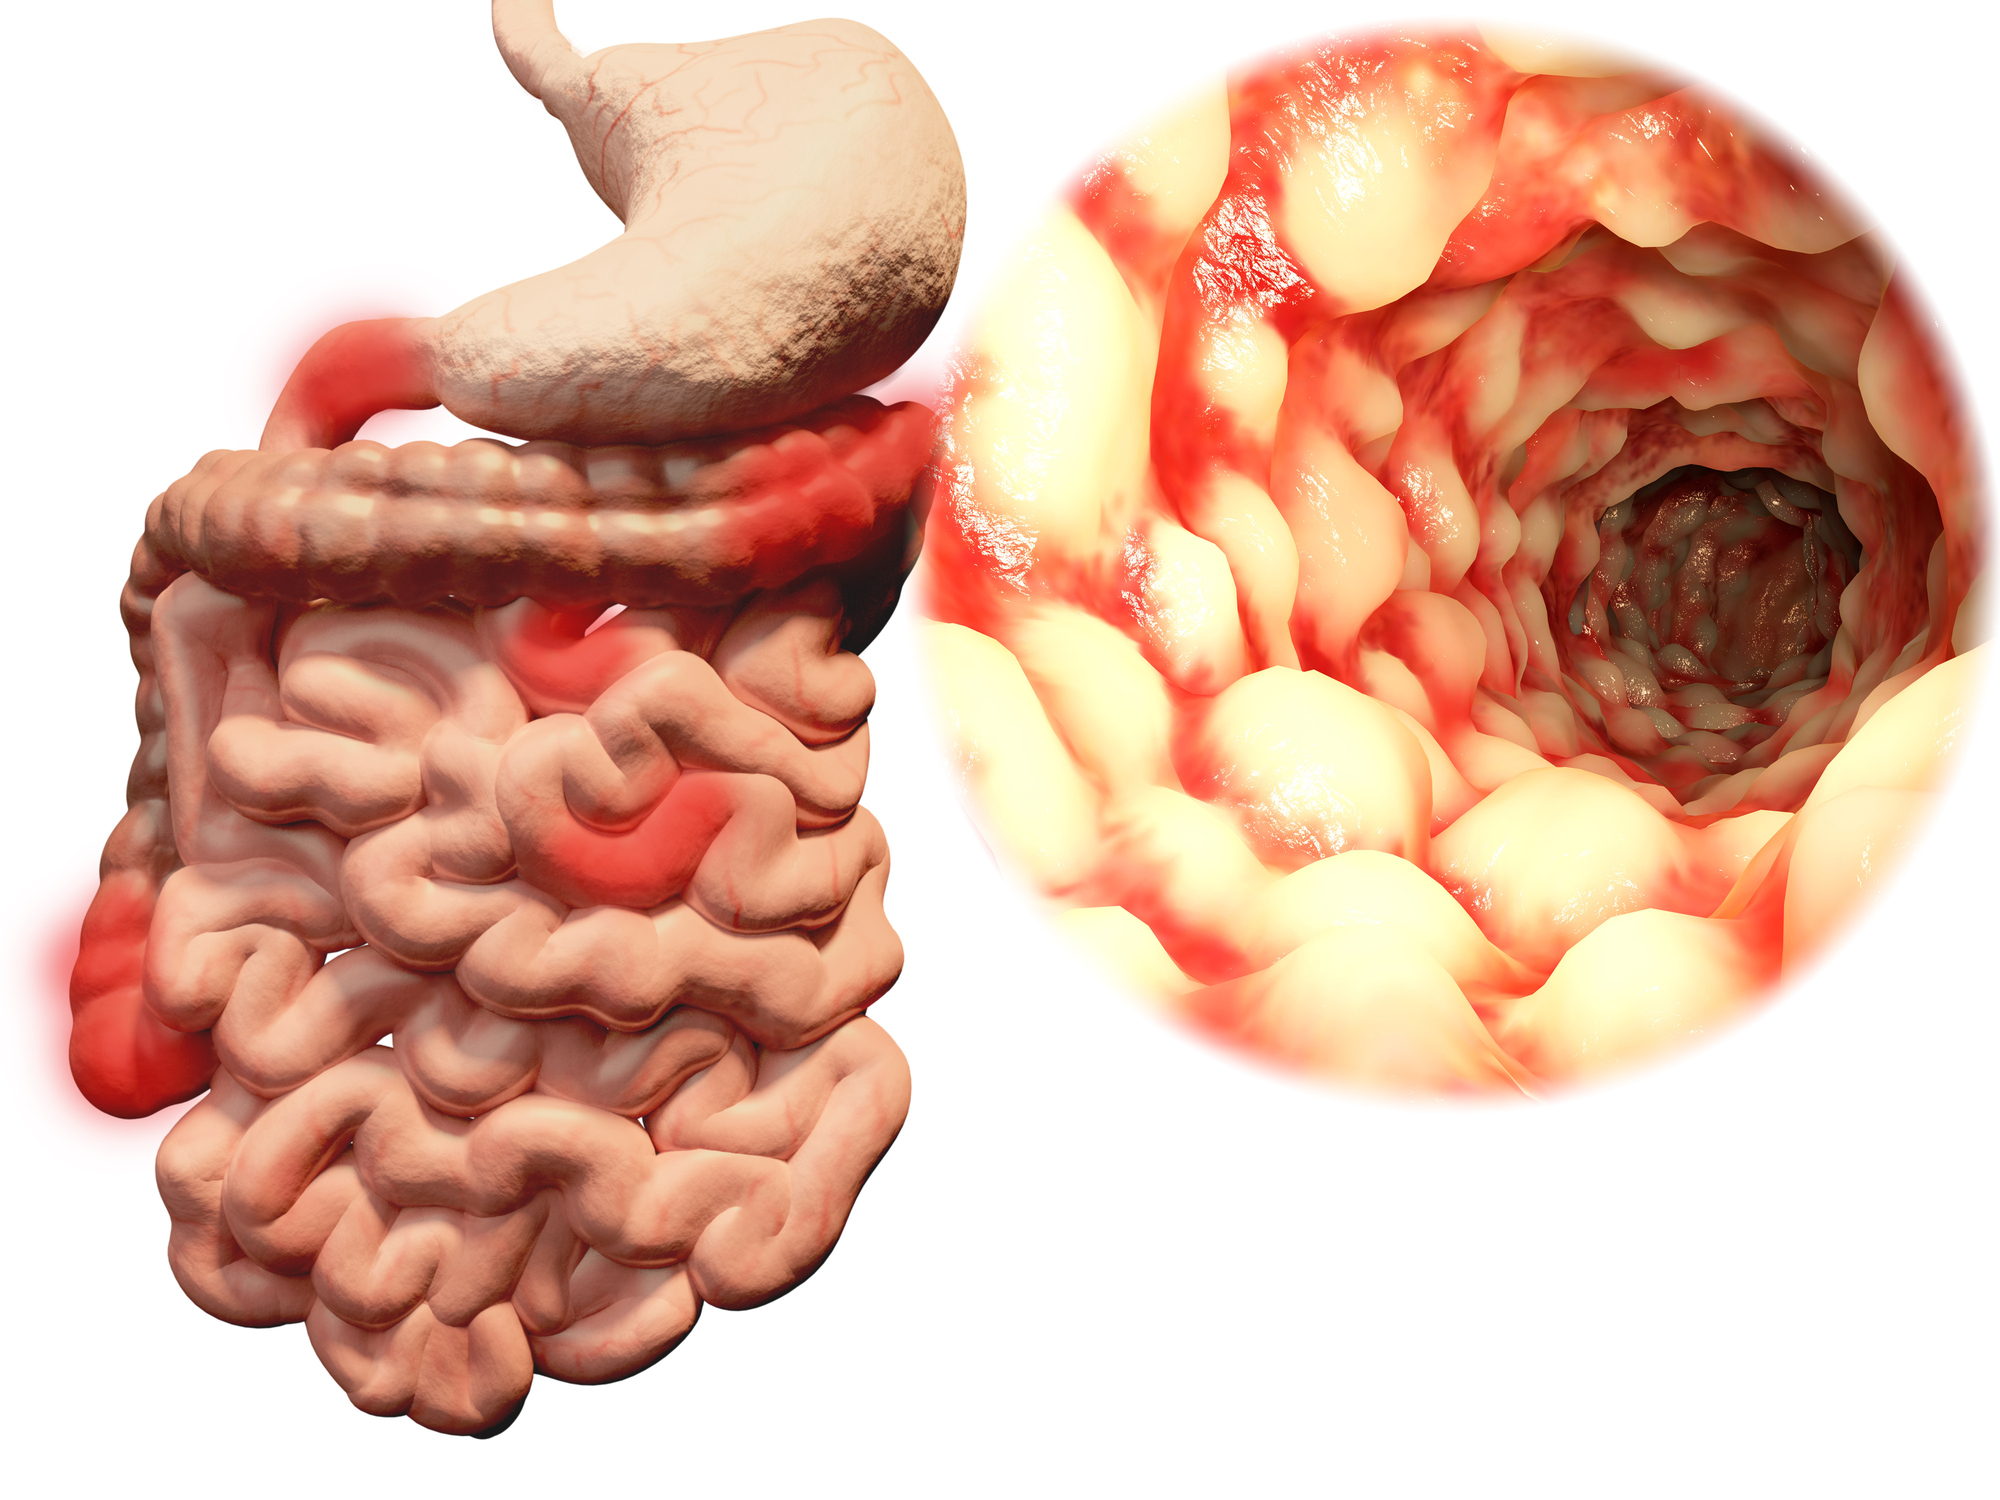

Inflammatory bowel disease (IBD) patients are sometimes misdiagnosed with irritable bowel syndrome (IBS). IBD researcher and United European Gastroenterology spokesperson Dr Michael Scharl said, “IBS has been estimated to affect at least 10 percent of the population in Europe, and it causes distressing symptoms that disrupt normal life. We have known for some time that ...click here to read more